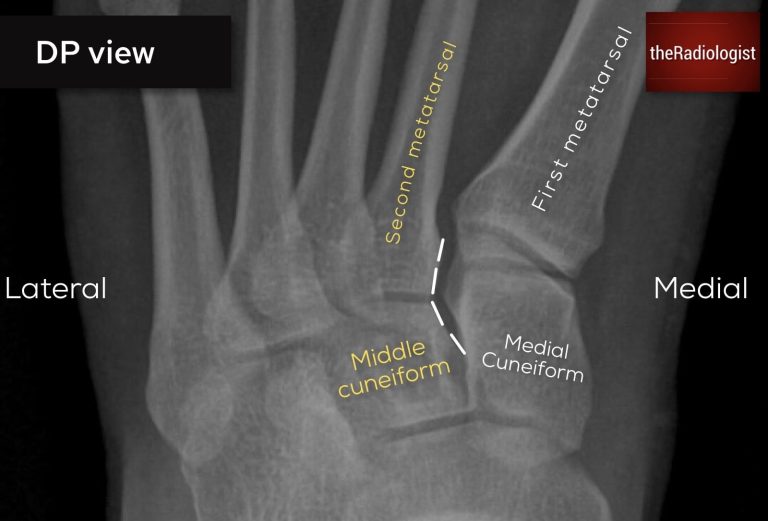

• DP view: the lateral borders of the 1st metatarsal and medial cuneiform should line up.

• DP view: the medial borders of the 2nd metatarsal and middle cuneiform should line up.

Looking for Lisfranc injury (DP view): on a DP view the lateral borders of the medial cuneiform and first metatarsal should line up as well as the medial borders of the second metatarsal and middle cuneiform

Looking for Lisfranc injury (DP view): in this case there is a subtle step between the middle cuneiform and the second metatarsal – this is a Lisfranc injury.